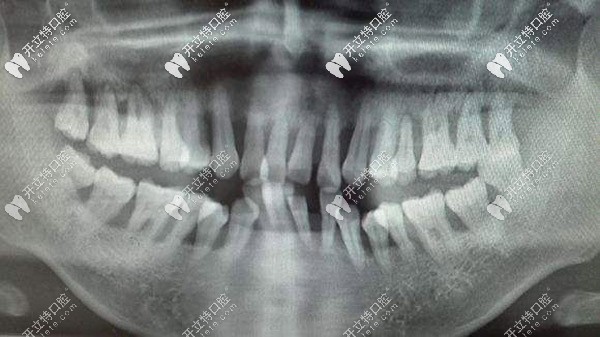

這就是侵襲性牙周炎的牙片

這就是侵襲性牙周炎的牙片▲

是真的!侵襲性牙周炎在臨床上的表現(xiàn)就是快速進展的牙周智齒組織破壞,它可以快速的讓牙周附著喪失和牙槽骨吸收。且發(fā)病的顧客年齡比較小,早期沒有明顯的癥狀。

一般等20-30歲確診后,病情就比較厲害了。像牙齦紅腫、增生、探診出血、深牙周袋、牙齒松動、移位或者脫落等癥狀的出現(xiàn)。它會導(dǎo)致顧客早早的失去牙齒……